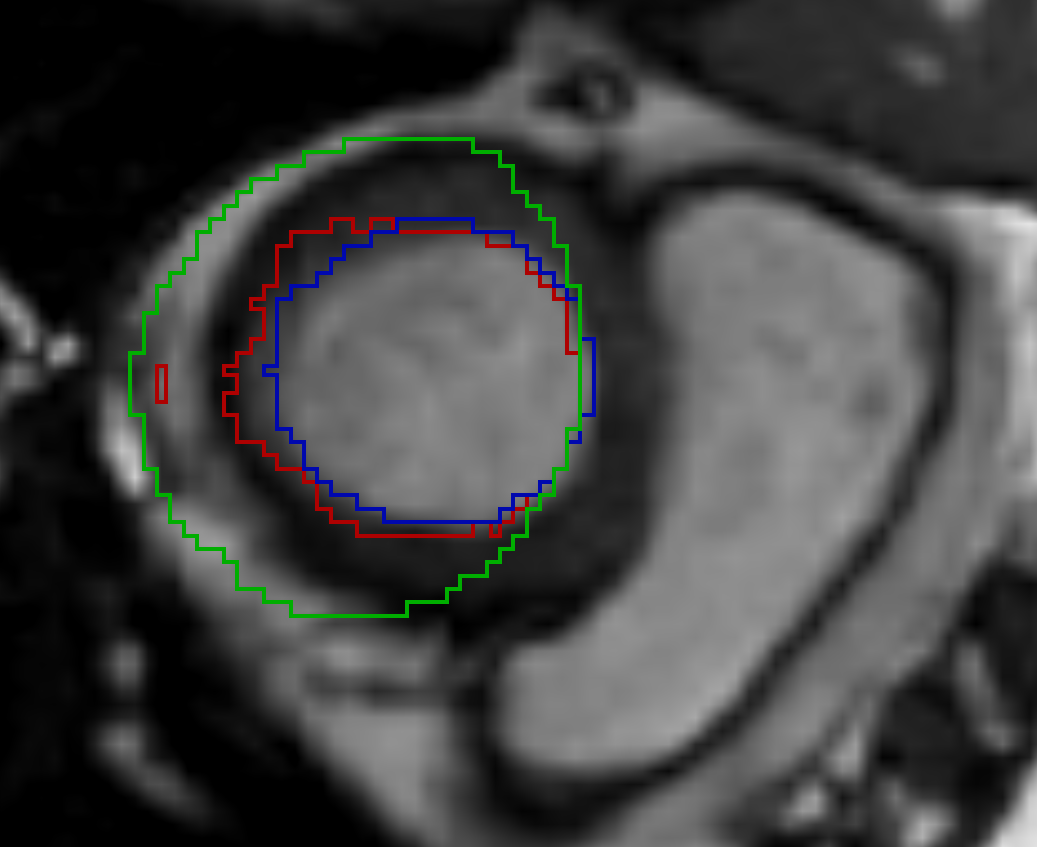

Refer to caption a) DirLab08 deformation grid for inhale to exhale registration Refer to caption b) DirLab08 with overlayed image foldings (Jacobi determinant << 0) Refer to caption c) DirLab08 registration error

Refer to caption d) SC-N-3 deformation grid for diastolic to systolic registration Refer to caption e) SC-N-3 with overlayed image foldings (Jacobi determinant << 0) Refer to caption f) SC-N-3 contours (green: input, blue: target, red: result)

Figure 5: This figures show an analysis for two test cases that resulted in the worst results for 3D registration evaluation. The first row shows the extreme inhale phase of dataset Dirlab08 with overlayed deformation grid (a), Jacobi determinant (b) and registration error (c). The patient had a very strong sheering motion along the ribcage in caudal direction which could not be fully captured by our network. The second row shows the extreme diastolic phase for the dataset SC-N-3 with overlayed deformation grid (d) and Jacobi determinant (e) and the extreme systolic phase with contours of the left ventricle (f).